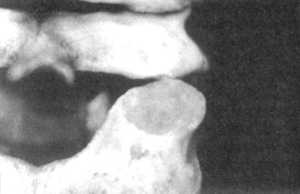

Рис. 2.15.1. Вытяжение с наклоном головы

вперед. Правый сустав. Вид сбоку |